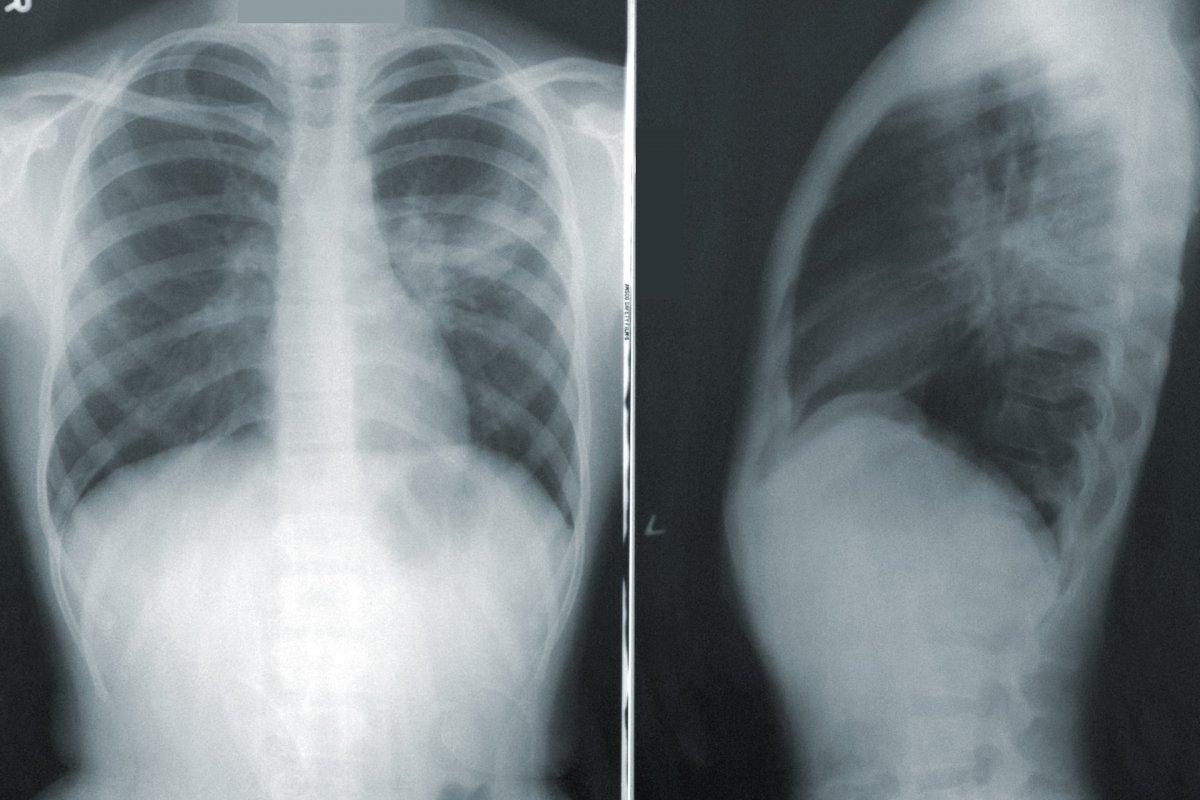

Рак легких признан самой смертоносной формой рака – тревожные сигналы, которые нужно заметить

Новое исследование показало, что рак легких является одним из самых смертоносных типов рака.